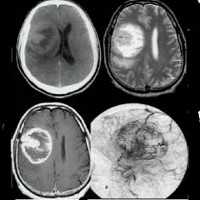

Глиобластома: симптомы, выявляемые с помощью МРТ. Аксиальный срез в режиме Т1 после контрастирования препаратом гадолиния демонстрирует распространенную опухоль правой лобной доли. Изображение предоставлено доктором George Jallo.

МРТ того же пациента. Т2-взвешенное изображение демонстрирует то же поражение, что и на предыдущем рисунке с заметным отеком и смещением срединных структур. Эти находки соответствуют высокой степени злокачественности опухоли.

Опухоль головного мозга — глиобластома. Компьютерная томография (КТ). Синяя звездочка в центре обозначает зону центрального некроза опухоли, заполненную жидкостью. Желтые стрелки — окружающий мягкотканный компонент опухоли. Красные звездочки — перифокальный отек мозга. Наблюдается смещение срединных структур и угроза нисходящего транстенториального вклинения мозга.

Как выглядит глиобластома на МРТ? Как правило, образование на томограммах представляет собой зону, имеющую в основном пониженный сигнал на Т1-взвешенных изображниях и повышенный сигнал на Т2- взвешенных изображениях. Могут присутствовать внутренние кистозные участки, участки потери сигнала, обусловленные крупными сосудами, внутренние зоны повышенной интенсивности сигнала на Т1-ВИ (геморрагические очаги), новообразованные сосуды, очаги некроза, обширный перитуморозный вазогенный отеком и значительный масс-эффект. Также может выявляться неравномерное, но интенсивное накопление контрастного вещества на основе гадолиния (та же картина наблюдается на КТ после введения йодсодержащего контраста), как в основной опухоли, так и в метастатических очагах, характерных для МФГ. МРТ более чувствительна к этим изменениям, чем КТ.